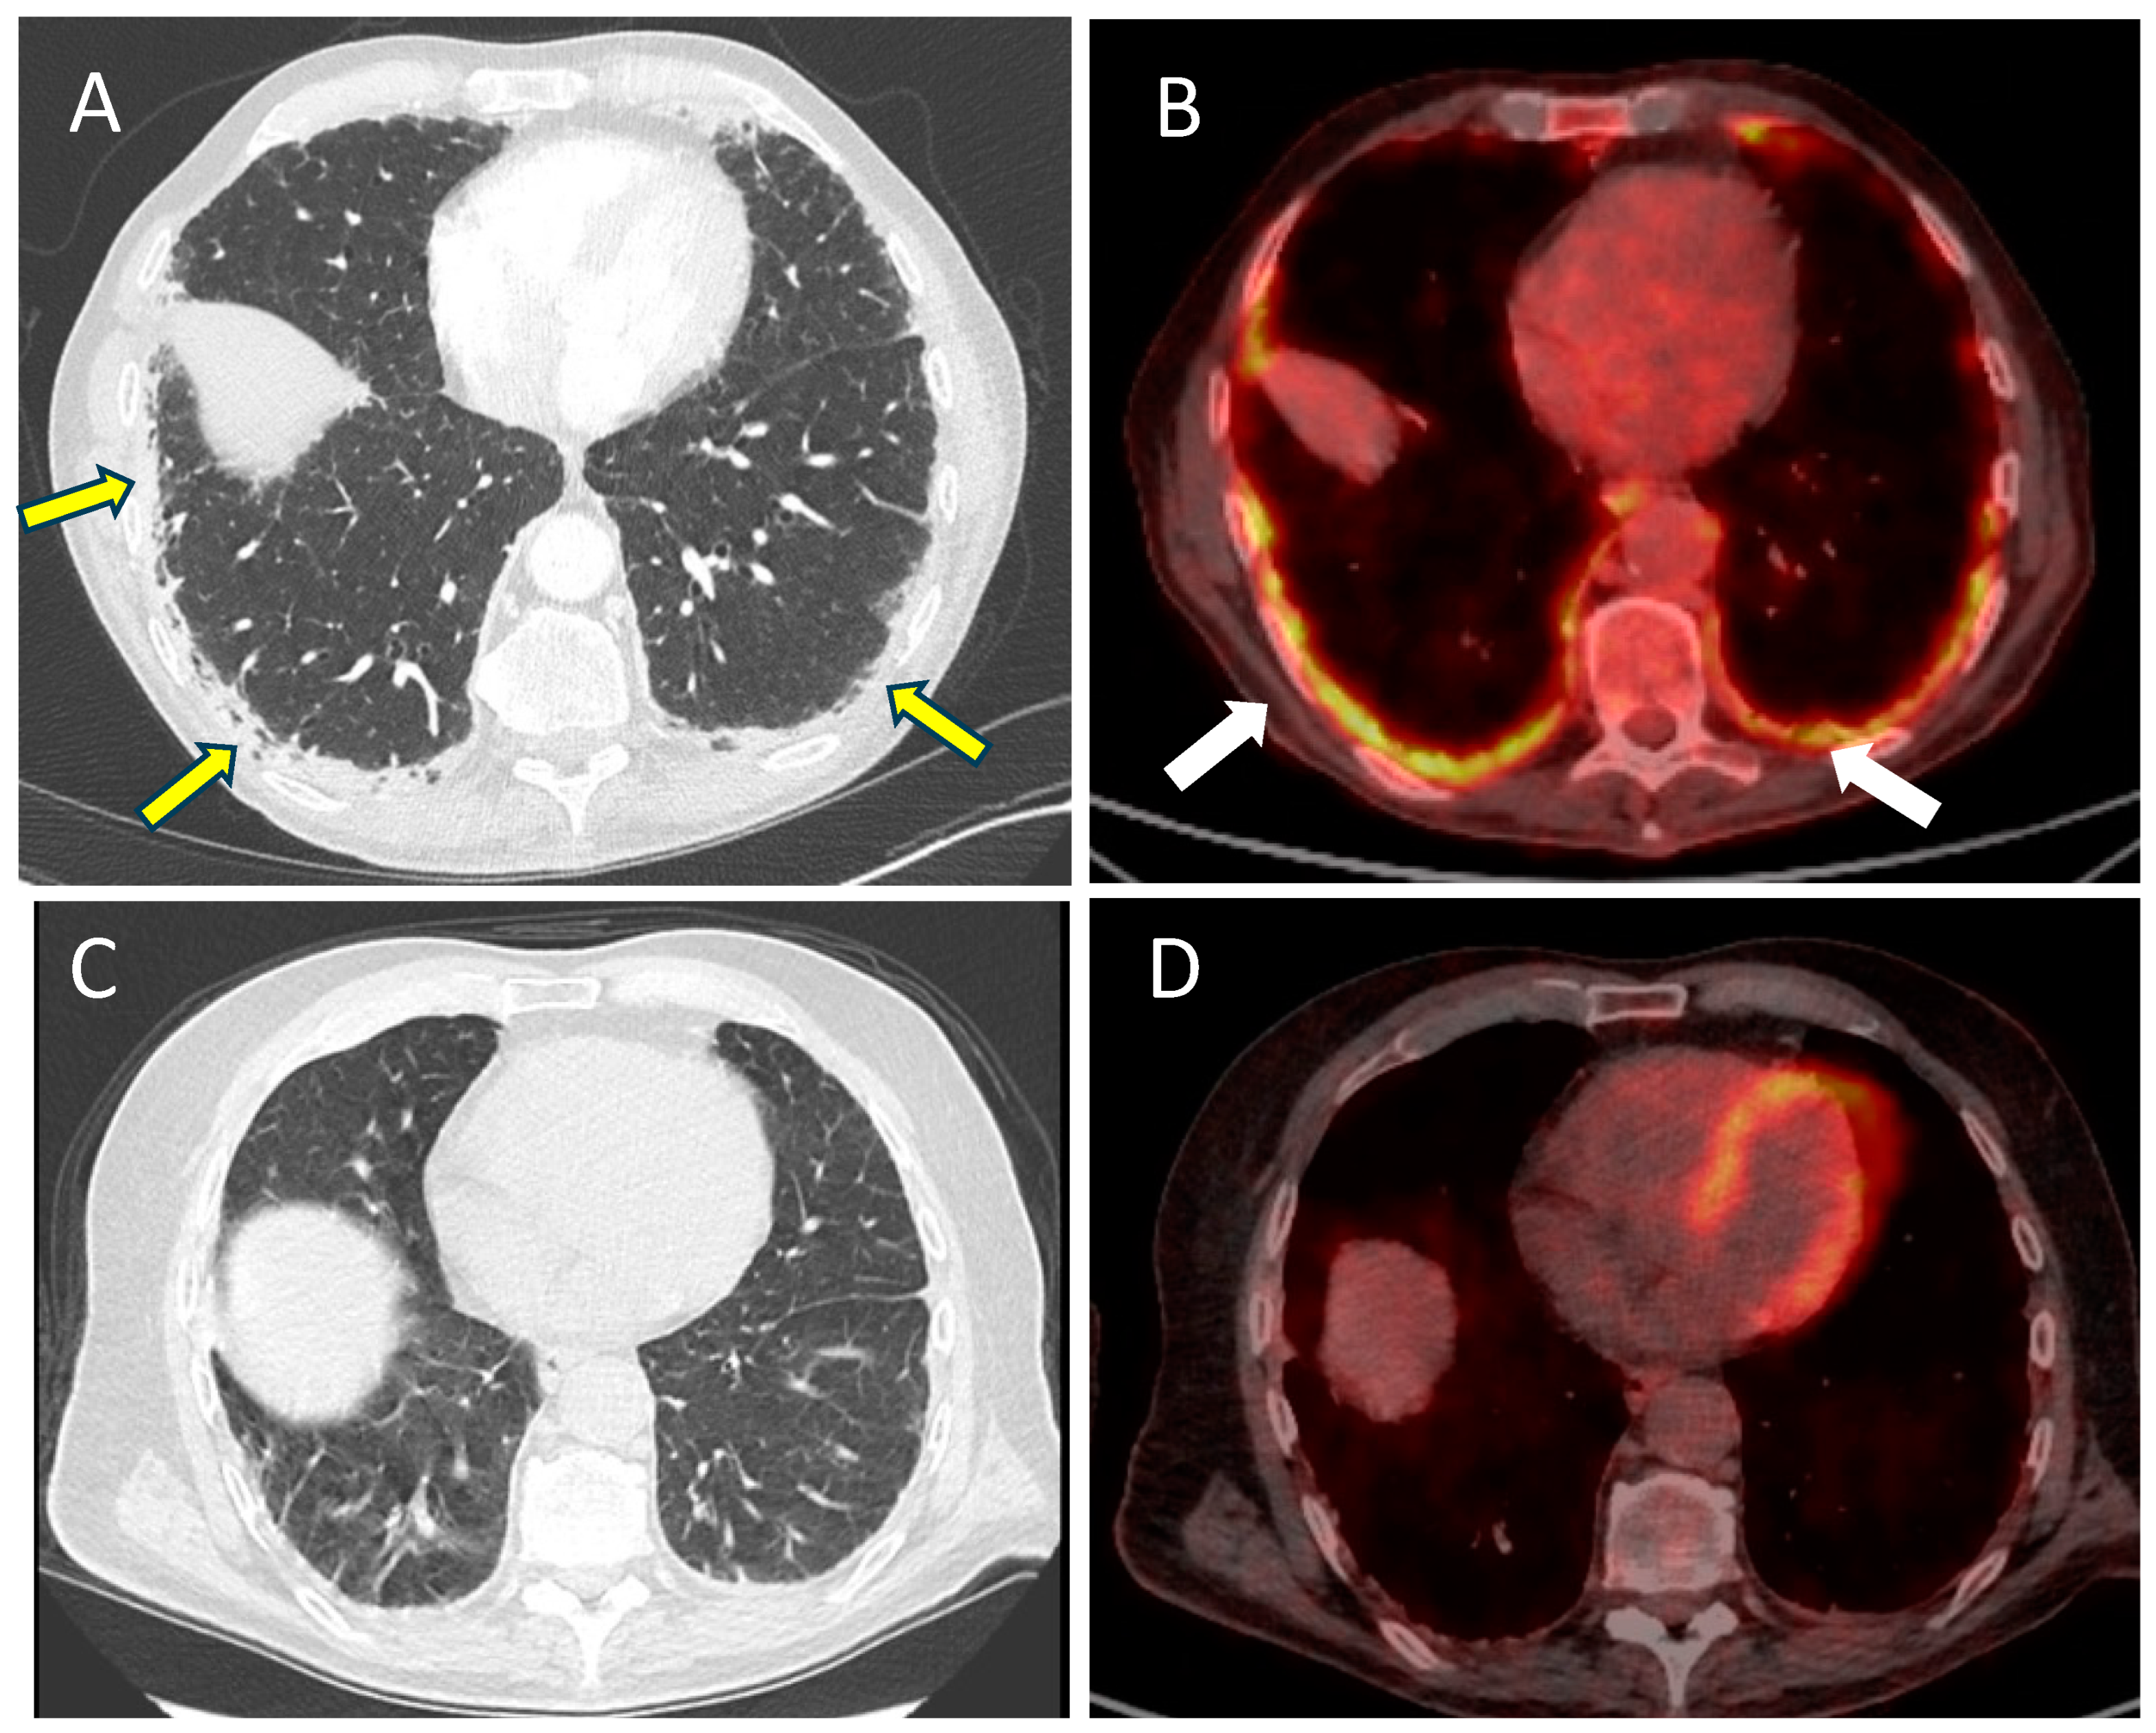

2.1. Case 1 (Priming Patient)